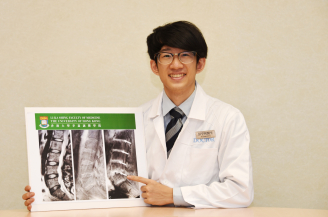

Dr Henry Pang, Master of Research in Medicine student, Li Ka Shing Faculty of Medicine, HKU and first author of the study, further noted that “Among various MRI sequences, UTE MRI is the only sequence so far in our study that showed definite correlation between back pain, disability and degenerative disc changes. At the same time, as our study group unveils the previously hidden pathologies in traditional MRI, these findings may promote further understanding in the pathologies and therapies for low back pain and lumbar degeneration.”

MRI of the lumbar spine of a subject with no chronic low back pain.

(Left) T2-weighted MRI noting multilevel disc degeneration and Modic changes.

(Right) Ultra-short time-to-echo (UTE) MRI noting no UTE disc sign (UDS).